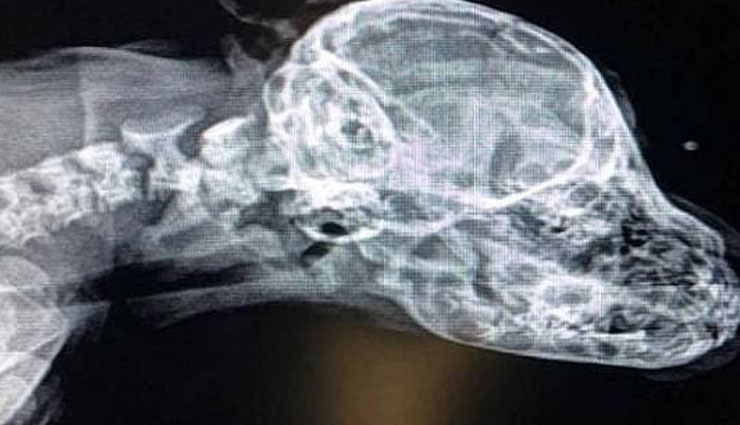

जिस बचाव अभियान दल ने इस कुत्ते का रेस्क्यू किया है उसके संस्थापक रोशेल स्टीफन का कहना है कि यह सचमुच जादुई चीज है जिसे आपने कभी देखा है। उन्होंने कहा कि हम उसे पाकर बहुत खुश हैं। रोशेल स्टीफन ने इस कुत्ते के पिल्ले का पशु अस्पताल में एक्स-रे कराया. रोशेल स्टीफन का कहना है कि हमें लगा कही पूंछ में हड्डी तो नहीं है जो आगे चलकर दिक्कत खड़ी करे। उसके एक्सरे को देखकर डॉक्टर भी चकित रह गए। पता चला कि नरवाल की इस दूसरी पूंछ में कोई हड्डी नहीं है।